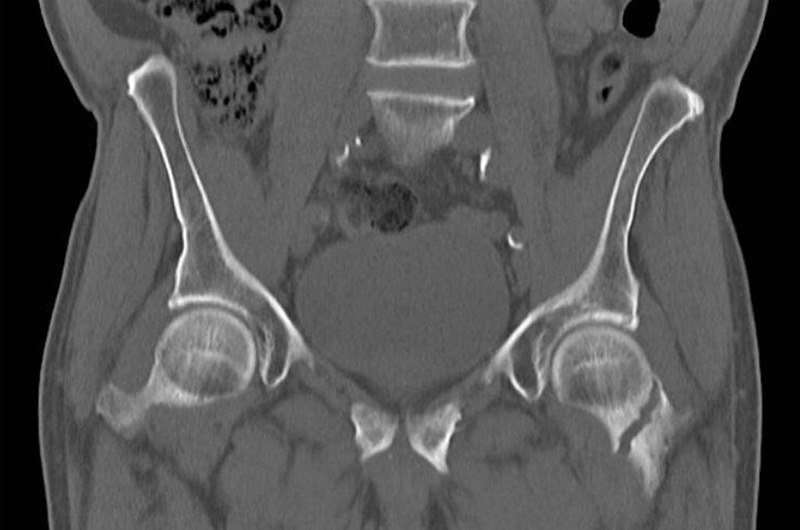

Компьютерная томография выдает детальные изображения мягких тканей, костей, связок в этой области. Исследование показывает:

- Артрит, воспаление. Томограмма визуализирует признаки воспаления при диагностике артрита, артроза, синовита.

- Дегенеративные изменения. Оценка степени износа суставных поверхностей, наличие остеоартроза.

- Травматические повреждения. Точное определение переломов, смещений, трещин, вывихов.

- Опухоли, кисты. Выявление новообразований, кист в тазобедренной области, их размеров, структуры.

- Структурные аномалии. Выявление врожденных аномалий развития головки бедра (дисплазия или мальформации).

Результаты КТ тазобедренного сустава обычно предоставляются радиологу, который проанализирует полученные изображения. Отчет содержит информацию о структуре костей, суставных поверхностях, мягких тканях, сосудах и других структурах. Врач произведет детальный анализ, выявит любые аномалии, патологии или изменения, даст заключение, на основе которого будет принято решение о дальнейших тактиках лечения.